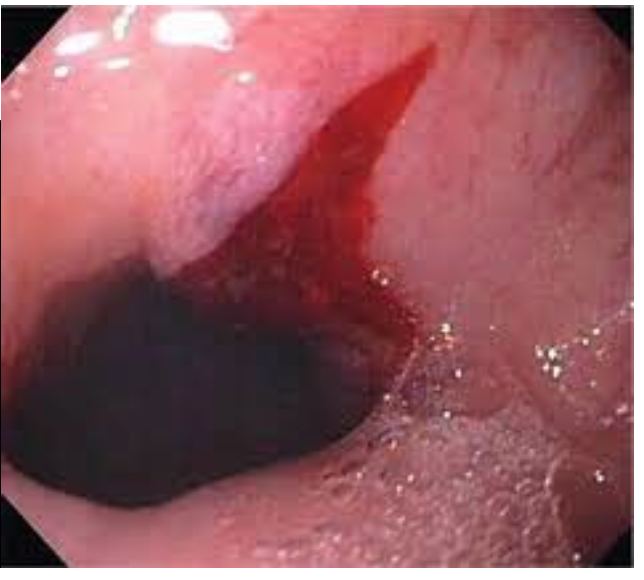

Cameron Lesion

manage with iron and PPI

HH repair if refractory